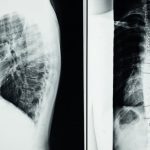

Le bombement discal, aussi appelé protrusion discale, se produit lorsque le gel interne du disque se déplace en direction de l’extérieur sans percer l’enveloppe discale. Cela peut provoquer des douleurs considérables et une limitation de la mobilité, car le disque enflammé peut exercer une pression sur les racines nerveuses environnantes. Cette condition requiert une attention particulière pour gérer la douleur et restaurer la souplesse.

Les bombements discaux, souvent causés par des mouvements répétitifs ou des lésions, sont des affections courantes qui impactent la qualité de vie des individus. la décompression neurovertébrale se présente comme une solution efficace pour ces problèmes, permettant de soulager la douleur et d’améliorer la fonction corporelle. En ciblant précisément les zones touchées, cette méthode aide à rétablir l’équilibre entre les structures vertébrales et à favoriser la guérison des tissus.